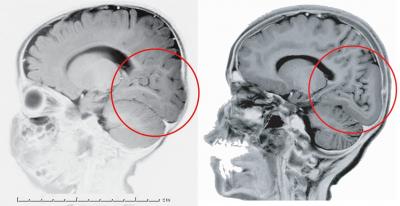

A genetic analysis of a Turkish patient whose brain lacks the characteristic convolutions in part of his cerebral cortex revealed that the deformity was caused by the deletion of two genetic letters from 3 billion in the human genetic alphabet. Similar variations of the same gene, called laminin gamma3 (LAMC3), were discovered in two other patients with similar abnormalities.

The folding of the brain is seen only in mammals with larger brains, such as dolphins and apes, and is most pronounced in humans. These fissures expand the surface area of the cerebral cortex and allow for complex thought and reasoning without taking up more space in the skull. Such foldings aren't seen in mammals such as rodents or other animals. Despite the importance of these foldings, no one has been able to explain how the brain manages to create them. The LAMC3 gene – involved in cell adhesion that plays a key role in embryonic development – may be crucial to the process.